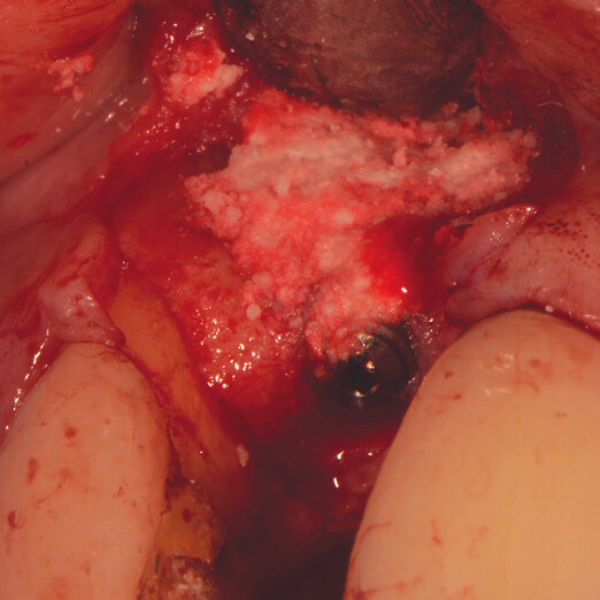

Resorbable Suture Tenting

Pain from a mobile upper right central incisor that had received trauma approximately ten years prior to presentation.